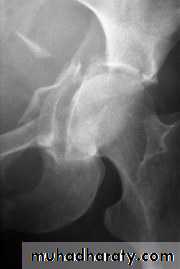

Radiological examination

two questions must be answered.Is there a fracture?

Is it displaced ?:Radiological classification

GRADE 1

:the femoral head is in its normal position or tilted into valgus and impacted on the femoral stump.GRADE 2

The femoral head is normally placed and the fracture line may be difficult to diagnosed

GRADE 3

The femoral head tilted out of position and the trabecular marking are not in line with those of innominate bone.GRADE 4

The femoral head trabeculae are normally aligned with those of innominate bone.